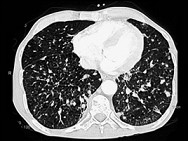

- 单项选择题女,56岁, 乳腺癌手术后,未行化疗, 结合CT图像,选择最可能的诊断是 ( )

A、肺转移癌

B、肺结核

C、间质性肺炎

D、肺结节病

E、肺曲菌病